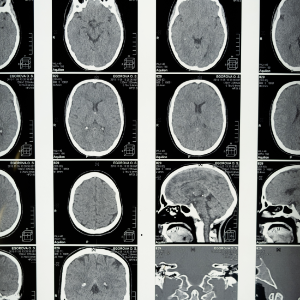

MRI나 CT 스캔과 같은 영상 진단 방법은 종양의 크기와 위치, 주변 조직과의 관계를 파악하는 데 매우 중요 합니다. 이러한 영상 자료는 수술 계획을 세우는 데 필수적인 정보를 제공해 줍니다.